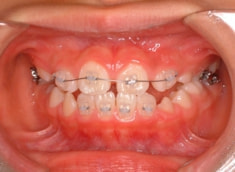

治療開始から3ヶ月後